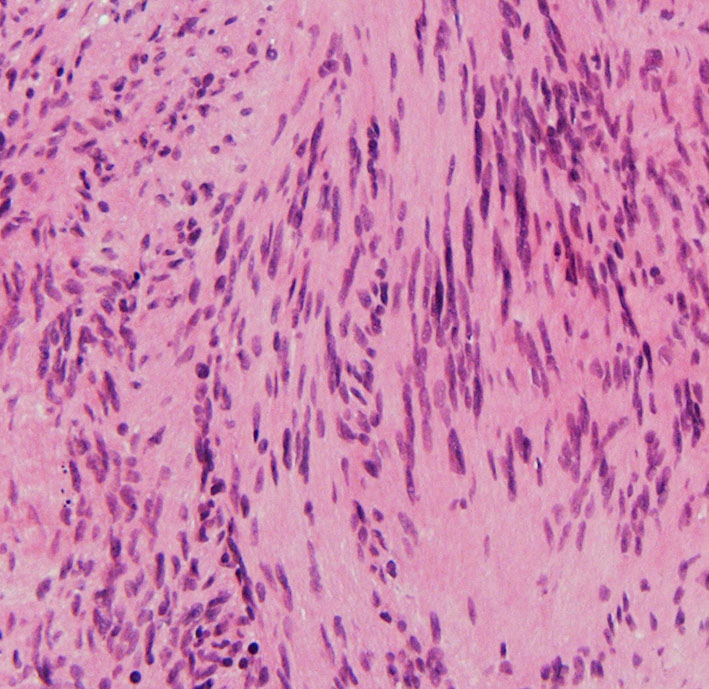

腫瘍細胞はS-100蛋白の免疫染色で陽性を示します。細胞密度が高くnuclear palisadingを示すAntoni type Aの部位(長い矢印)と細胞が比較的粗に配列するAntoni type Bの部位(短い矢印)でも陽性となります。S-100 x100.

紡錐型の核を有する腫瘍細胞で構成されます。左側の写真のように,古典的病理所見として,束状 fascicular に配列する密な組織である Antoni A Typeと網状 reticular で疎な組織である Antoni B Typeが混在するパターンを示します。神経鞘腫では多少の核の異型性がみられても悪性像とはいえません。嚢胞を形成したり,時には毛細血管拡張 simple hemangioma を思わせるような著明な血管の増生があり腫瘍内出血をきたすことがあります。